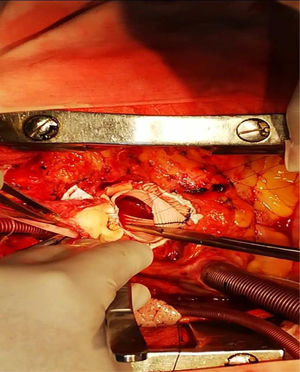

Realizamos una esternotomía con sierra oscilante, por medio de la cual encontramos abundantes adherencias por tratarse de una reoperación. Este procedimiento se efectuó con circulación extracorpórea (canulación aórtica, cava, seno coronario y vent en la arteria pulmonar). Posteriormente, continuamos con la aortotomía, en la cual se presentó un gran aneurisma hacia el seno coronario izquierdo (fig. 6).

Dentro del aneurisma, retiramos un abundante hematoma sobre el ostium de la coronaria izquierda, se extrajo el hematoma (fig. 7) y se observó tejido sanioso en vía de fistulizarse hacia la aurícula izquierda (fig. 8).

Con respecto a la coronaria izquierda, se pudo liberar del fondo del aneurisma, por lo cual se logró reimplantar sin tensión en la prótesis de Dacrón. La válvula era de aspecto sano trivalva y se colocó la prótesis de Dacrón sin afectarla, comprobando la buena funcionalidad luego de concluir la sutura en la raíz. Posteriormente, se realizó la técnica de Yacoub con preservación valvular y el reimplante coronario izquierdo, así como la exclusión del aneurisma del seno de Valsalva (ASV). El procedimiento se llevó a cabo con el tubo de Dacrón número 28. (figs. 9 y 10). El ecocardiograma intraoperatorio mostró buena competencia valvular e insuficiencia leve. El postoperatorio fue de buena evolución, la paciente fue extubada a las tres horas después de la intervención, sin sangrado significativo. Se dio el alta al séptimo día.